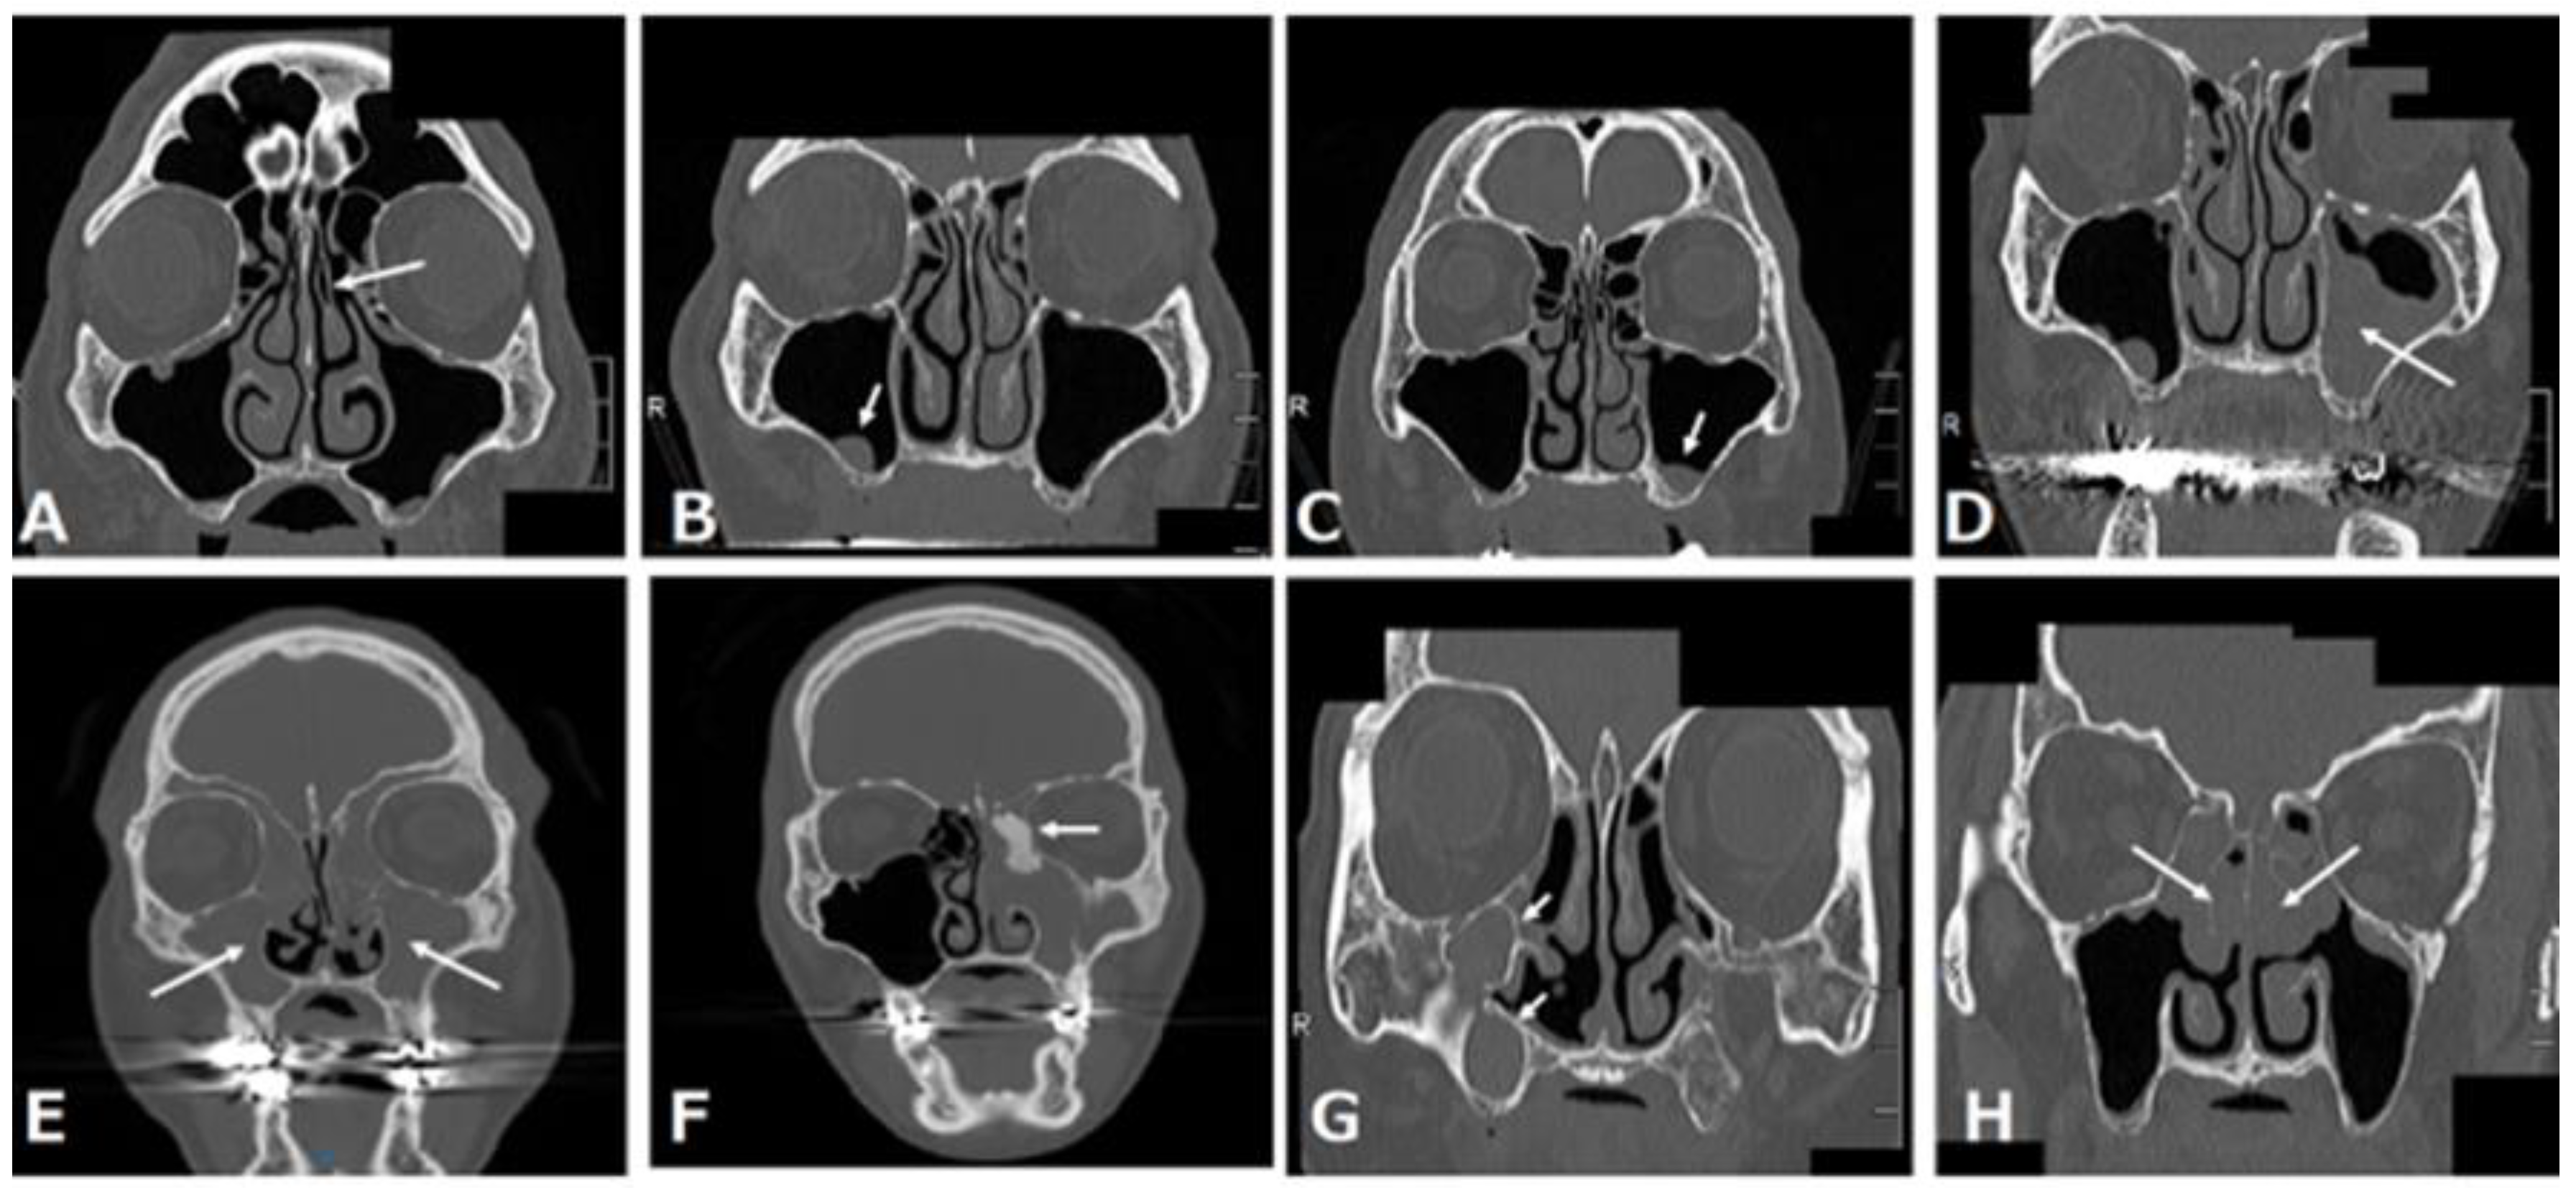

The common maxillary sinus pathologies that can be identified on coronal CT images of the paranasal sinus at our institution are shown in Figure 5. These pathologies are classified into three pathologies: those that need treatment, those that do not need treatment, and those that are not candidates for maxillary implantation. A normal maxillary sinus, retention cyst or solitary polyp, and mucosal thickening in the maxillary sinus do not need treatment before maxillary implantation (Figure 5A–C), whereas preoperative sinusitis needs treatment because it is a cause of the development of postoperative maxillary sinusitis (Figure 5D–F) [17]. Patients with a postoperative maxillary cyst also need treatment (Figure 5G). Patients with eosinophilic chronic rhinosinusitis are not suitable for maxillary implantation (Figure 5H).

Figure 5.

(A) Almost normal maxillary sinus and left concha bullosa of the middle turbinate (arrow); (B) retention cyst or solitary polyp in the right maxillary sinus (arrow); (C) mucosal thickening in the left maxillary sinus (arrow); (D) air-fluid level or fluid accumulation in the left maxillary sinus (most often indicating acute rhinosinusitis) (arrow); (E) total opacification of the maxillary sinus or other paranasal sinuses (most often indicating chronic rhinosinusitis) (arrow); (F) left chronic sinusitis with ethmoidal osteoma (arrow); (G) right two postoperative maxillary cysts (POMC) (arrow); (H) eosinophilic chronic rhinosinusitis (arrow).

3.1. Retention Cyst or Solitary Polyp

A retention cyst is described as one of the most common pathological findings of the maxillary sinus and usually presents as a dome-shaped radiopaque soft-tissue mass attached to the bony walls of the sinus (Figure 5B). Retention cysts are benign lesions that can originate from the accumulation of fluids inside the sinus membrane, which result from a ductal obstruction of the seromucous glands [18]. When patients with a small retention cyst or polyp have no complaints, ENT treatments are not required. Furthermore, the placement of dental implants after a sinus lift in patients with retention cysts is safe and presents a high chance of survival, regardless of whether the lesion is removed [19]. Therefore, we think that patients with a small cyst or solitary polyp in the maxillary sinus can still receive a maxillary implant with or without a sinus lift.

3.2. Mucosal Thickening in the Maxillary Sinus

Patients with mucosal thickening that is less than one-third to one-half of the maxillary sinus height and localized to the lesion around the teeth (Figure 5C) can still receive a maxillary implant with or without a sinus lift [20,21].

3.3. Acute Rhinosinusitis

Rhinosinusitis is defined as inflammation of one or more paranasal sinuses; acute rhinosinusitis is defined by symptoms such as nasal congestion, rhinorrhea, facial pain, hyposmia, and sneezing, which last less than 12 weeks [22]. Imaging often indicates air-fluid levels or fluid accumulation (Figure 5D). After the possibility of coronavirus disease 2019 (COVID-19) is ruled out by a severe acute respiratory syndrome coronavirus 2 (SARS-CoV-2) RT-PCR test—because the clinical manifestations of rhinosinusitis are similar to the symptoms of COVID-19 [23] and patients recover from the illness by conservative ENT treatment—they can still receive a maxillary implant with or without a sinus lift.

3.4. Chronic Rhinosinusitis

Chronic rhinosinusitis is defined as symptoms that last more than 12 weeks [22]. Chronic rhinosinusitis is classified into two categories: neutrophilic and eosinophilic. Furthermore, neutrophilic chronic sinusitis has two patterns: with or without a benign tumor.

3.4.1. Neutrophilic Chronic Rhinosinusitis

CT often shows almost all opacification of the maxillary sinus or other paranasal sinuses (Figure 5E). After conservative and/or surgical treatment by FESS, patients can still receive an implant treatment with or without a sinus lift [24].

3.4.2. Neutrophilic Chronic Rhinosinusitis with a Benign Tumor Such as Osteoma

Neutrophilic chronic rhinosinusitis with a benign tumor in the paranasal sinuses is a subtype of neutrophilic chronic sinusitis (Figure 5F). This disease can be considered to result from the obstruction of the natural ostium of the maxillary sinus by the tumor. The surgical options for this disease are an endoscopic procedure or a combined external and endoscopic procedure [25]. If a surgeon selects the former and can achieve complete resection, patients can still receive a maxillary implant with or without a sinus lift. Otherwise, when a surgeon selects the combined approach, dentists should consider the possibility of a postoperative maxillary cyst (POMC) at the time of the maxillary implant.

3.4.3. Eosinophilic Chronic Rhinosinusitis (ECRS)

ECRS is recognized as refractory chronic rhinosinusitis despite the combination of macrolide therapy and FESS, which is effective for neutrophilic chronic rhinosinusitis [26]. ECRS has a strong tendency for recurrence after FESS. CT scan images of ECRS patients show them to be ethmoid-sinus-dominant (Figure 5H), while CT of neutrophilic chronic sinusitis shows maxillary predominance in the early stages. Patients with ECRS tend to be more likely to develop rhinosinusitis symptoms after maxillary implant treatment, so they are not suitable for implant treatment or other prostheses such as dentures; implant-supported overdentures are recommended as an alternative method to avoid maxillary implant treatment [27].

3.5. POMC

POMC is a delayed complication of maxillary sinus surgery, such as Caldwell–Luc surgery, which is a radical technique used to remove infection and diseased mucosa from the maxillary sinus (Figure 5G). Marsupialization with drainage of a POMC should be performed before the insertion of an implant, in order to prevent implant failure resulting from possible bone destruction around the dental implant following the expansion of the POMC [28].